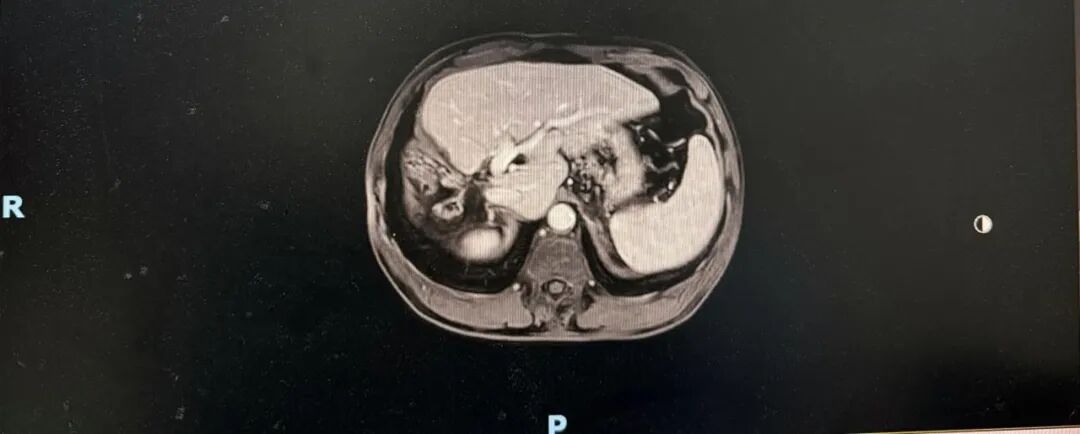

➣ 2019年4月23日,腹部增强CT:右肝巨块型肿块,大小约16*15*10cm,伴周围子灶形成;右肝静脉、门静脉右后支受侵;肿块体积 1236.63㎝³,左肝体积 863.97㎝³。

疗效评价1

mRECIST评价标准:PR

➣ 目标病灶(动脉期增强显影)的直径总和缩小>30%

肿瘤体积明显缩小:749.25⁄1236.63 cm³ ≈60%